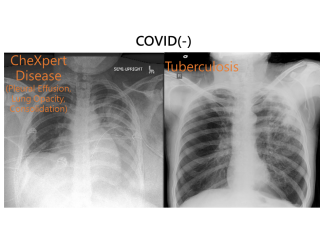

Artificial Intelligence Application——The 5 Most Promising Industries for AIArtificial Intelligence Application——The 5 Most Promising Industries for AIWith the entry of AI into human life, the face of various industries has changed. Among them, the medical industry is particularly outstanding. The MAIA platform developed by the Muen team is the world's first automated AI platform developed specifically for the medical field.

Artificial Intelligence Application——The 5 Most Promising Industries for AIArtificial Intelligence Application——The 5 Most Promising Industries for AIWith the entry of AI into human life, the face of various industries has changed. Among them, the medical industry is particularly outstanding. The MAIA platform developed by the Muen team is the world's first automated AI platform developed specifically for the medical field. -